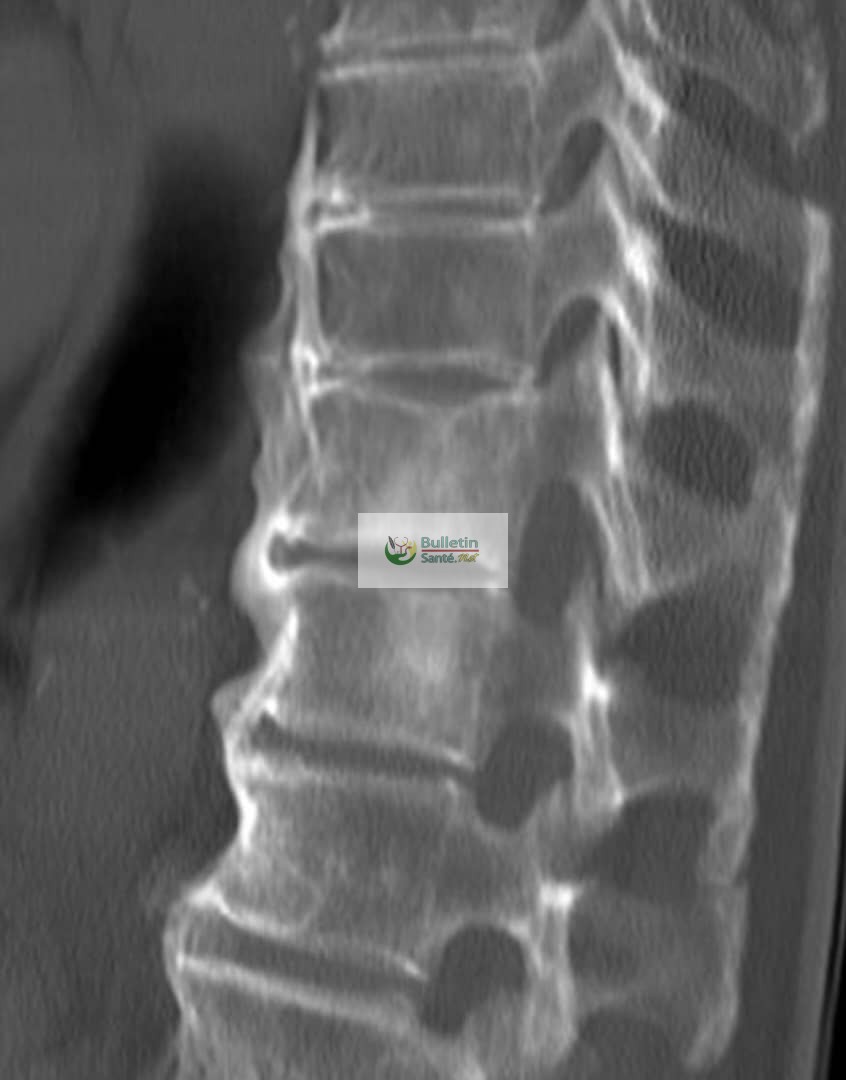

La maladie de Forestier, aussi appelée hyperostose vertébrale, est une affection où les ligaments et les tendons autour des vertèbres deviennent durs et se transforment en os. Cela crée comme des ponts osseux entre les vertèbres de la colonne, ce qui peut rendre le dos raide. Plus fréquente chez les hommes après la cinquantaine que chez les femmes, elle peut toucher le cou, le haut ou le bas du dos.

Comme l’explique le Dr Binta Yaro Savadogo, médecin spécialiste des os et des muscles, la maladie ne donne souvent pas de signe au début. Elle est parfois découverte par hasard lors d’une radiographie. Mais chez certains, elle provoque des douleurs dans le dos et une difficulté à bouger facilement, surtout le matin ou après être resté longtemps sans bouger.